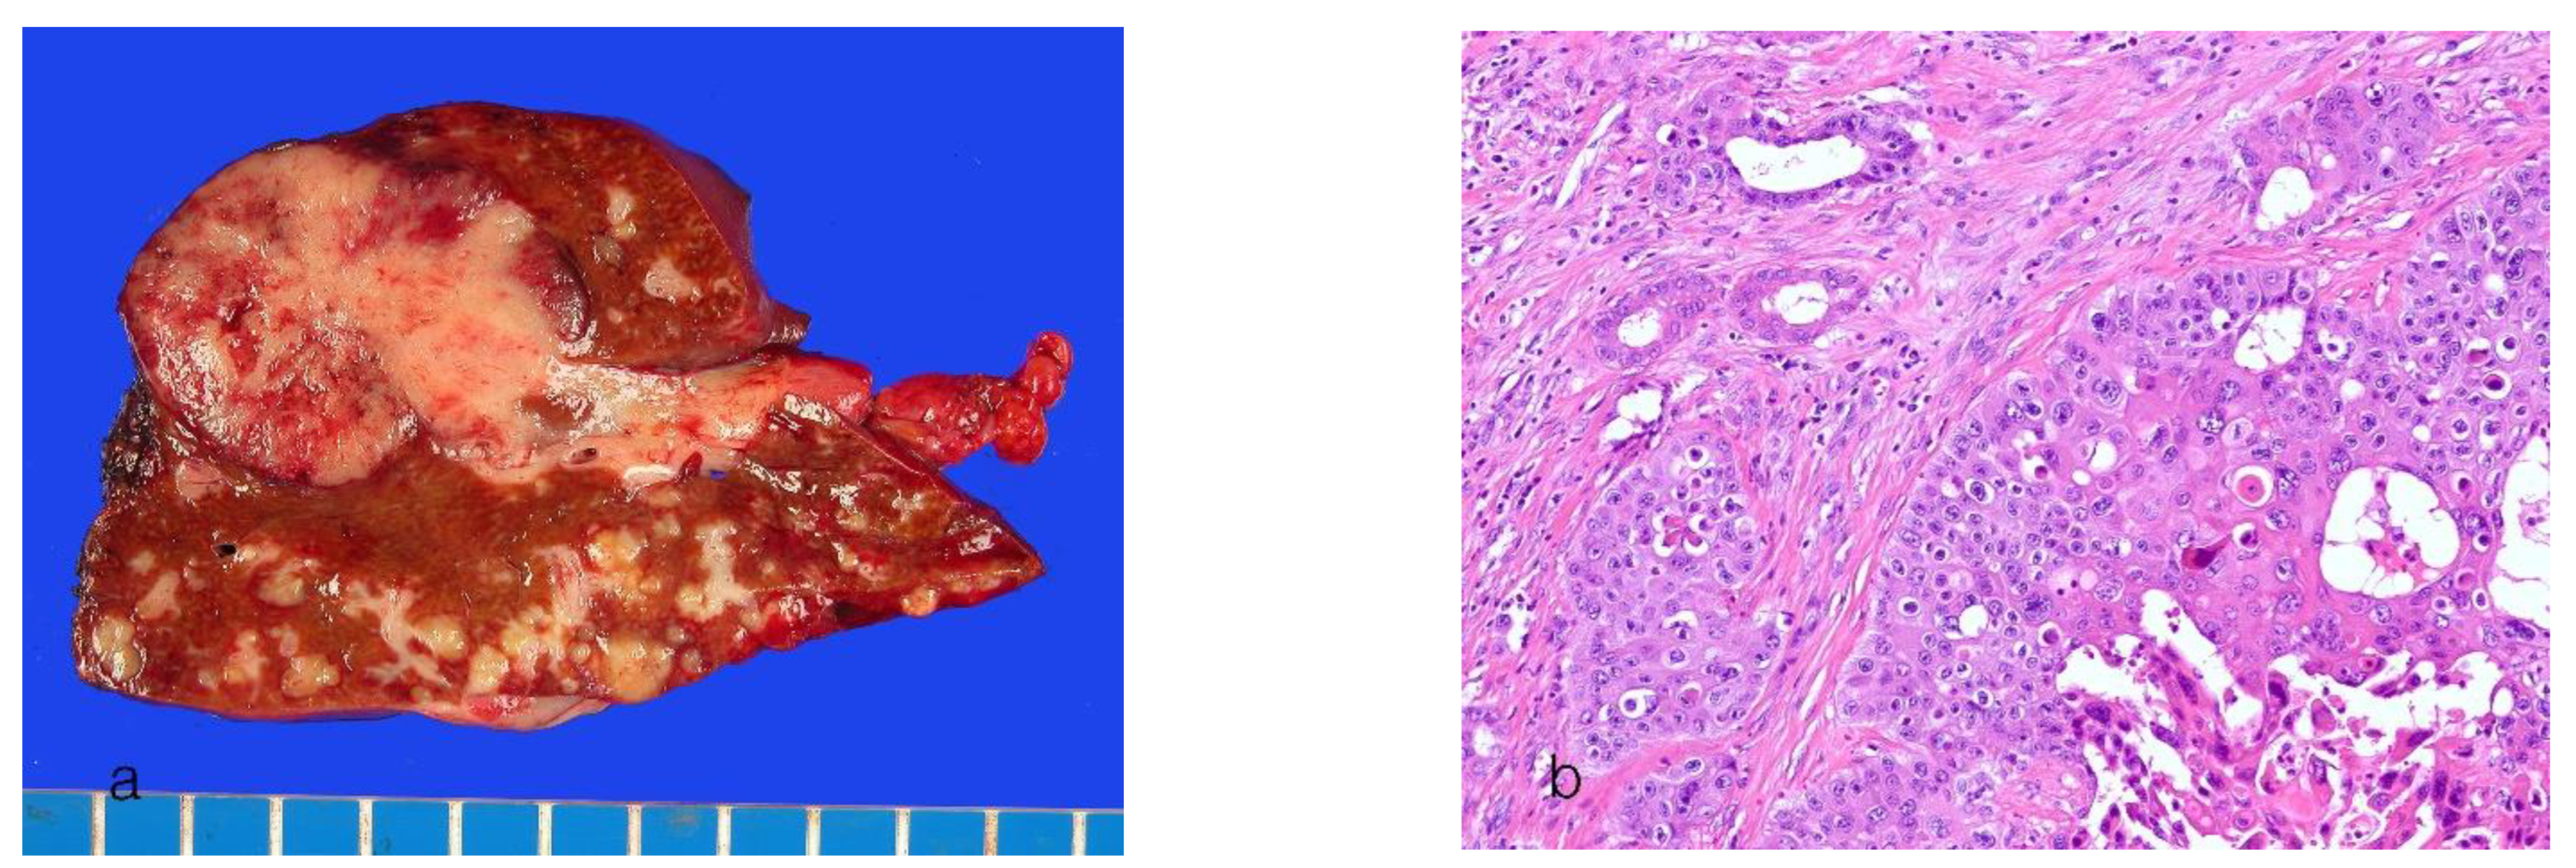

8.2. Large-Duct Intrahepatic Cholangiocarcinoma

| Histology | Small-ductal components: tubular pattern with low columnar to cuboidal cells and desmoplastic reaction Ductular components, cuboidal epithelia showing ductular or cord-like pattern with slit-like lumen and desmoplastic reaction | Ductal or tubular pattern with columnar to cuboidal epithelium, with desmoplastic reaction |